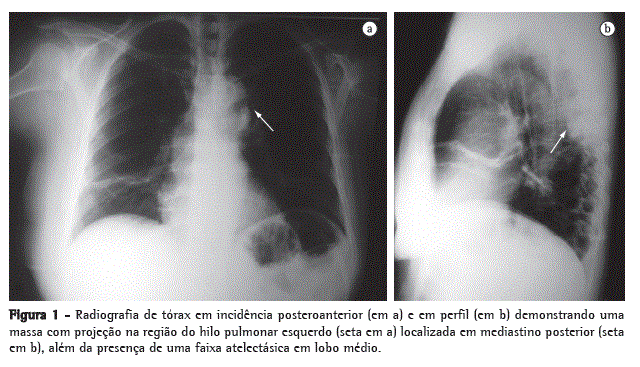

A radiografia de tórax evidenciou uma massa em topografia de mediastino posterior, que foi confirmada no pré-operatório por TC de tórax, na qual foi identificada uma massa heterogênea com calcificação densa em topografia de goteira costovertebral esquerda (Figuras 1 e 2).